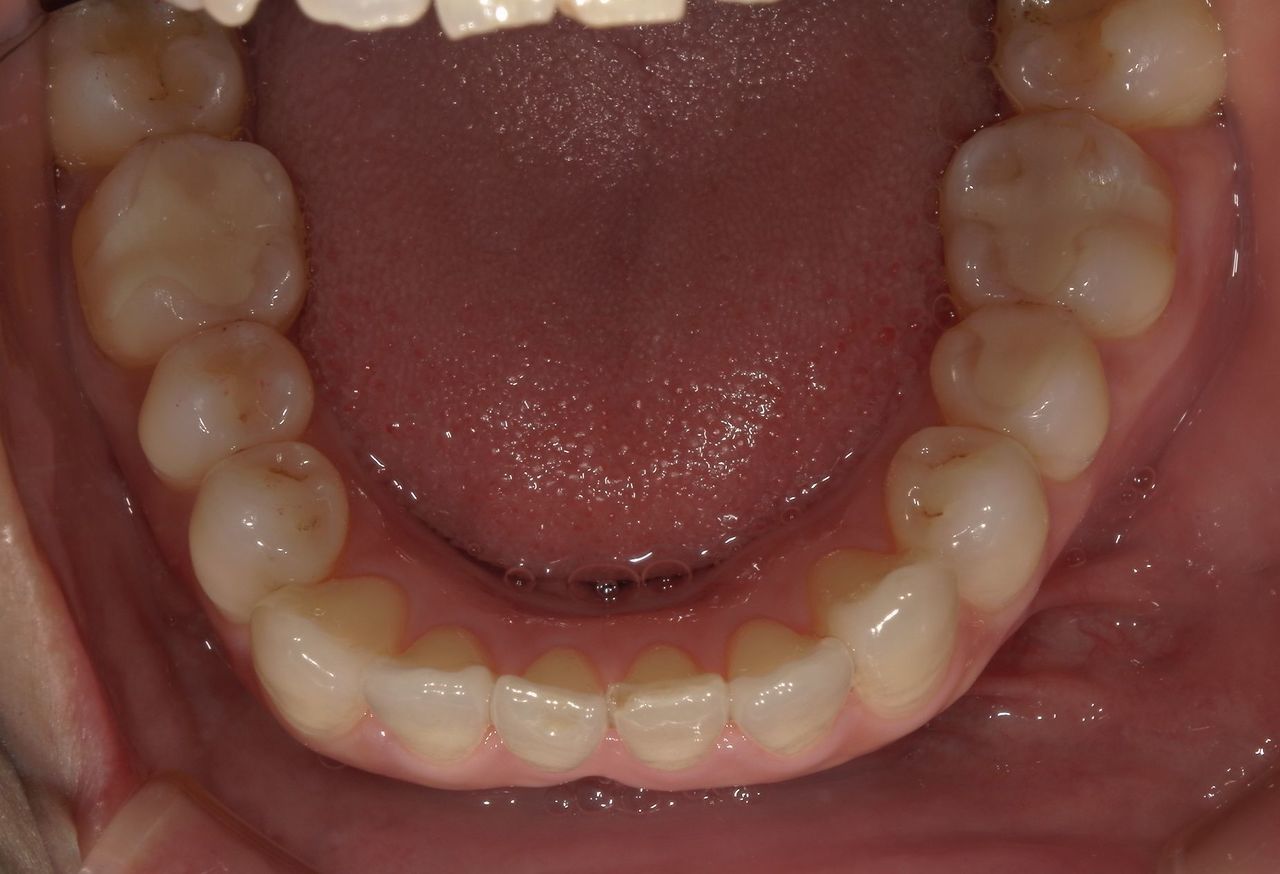

左下6番目に銀歯が装着されている。

銀歯を外して、虫歯を削ってから保険適応の詰め物をした。